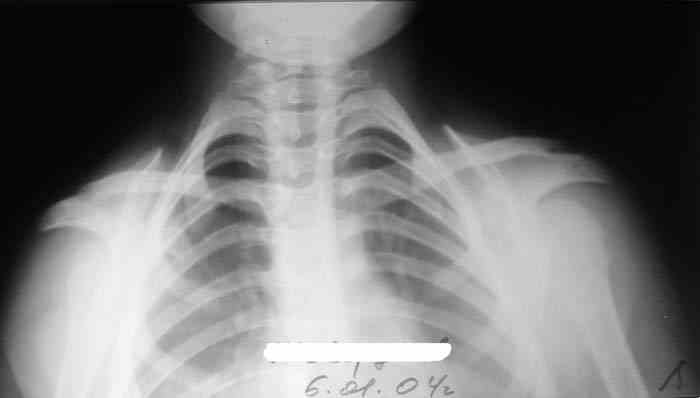

Девочка, 9 лет. Жалобы на деформацию верхнего плечевого пояса.

Объективно: приведение обоих надплечий, объем движений в плечевых суставах в полном объеме, общесоматический статус без патологии, УЗИлопаточных областей - без патологии.

Возможно речь идёт о добавочных шейных рёбрах, для уточнения целесообразно сделать боковую рентгенографию.

По МКБ-10 шейное ребро С6;С7. Вот ссылка:http://www.ristar.ru/info/references/mkb/1385/1448/1460

Больная на Вашей фотографии довольно похожа на Cleidocranial Disostosis. Пришлите снимки плечевого пояса. Это может быть недоразвитие или отсутствие ключиц.

Наличие ключиц на прямом снимке, снимает диагноз врожденного отсутствия ключиц.

Мне кажется, случай похож на Poland's Syndrom, синдром встречается при врожденной паталогии, когда отсутствует грудные мышцы (pectoralis), в большинстве случаев односторенне, и пластические хирурги рекомендует операцию.

Предлагаю пока рабочим диагнозом считать: "Врожденная аномалия грудной клетки. Добавочные шейные ребра".